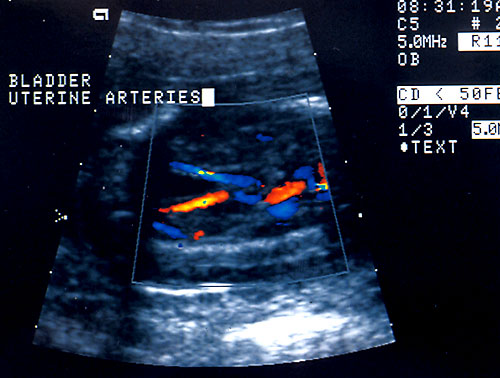

Normal fetal bladder at 18 weeks (left, at arrow). Lovely picture of both uterine arteries around normal bladder (right). This color flow picture documents the presence of the 3 vessel cord with the demonstration of the two uterine arteries coursing around the bladder. - Spine (need two perpendicular views)